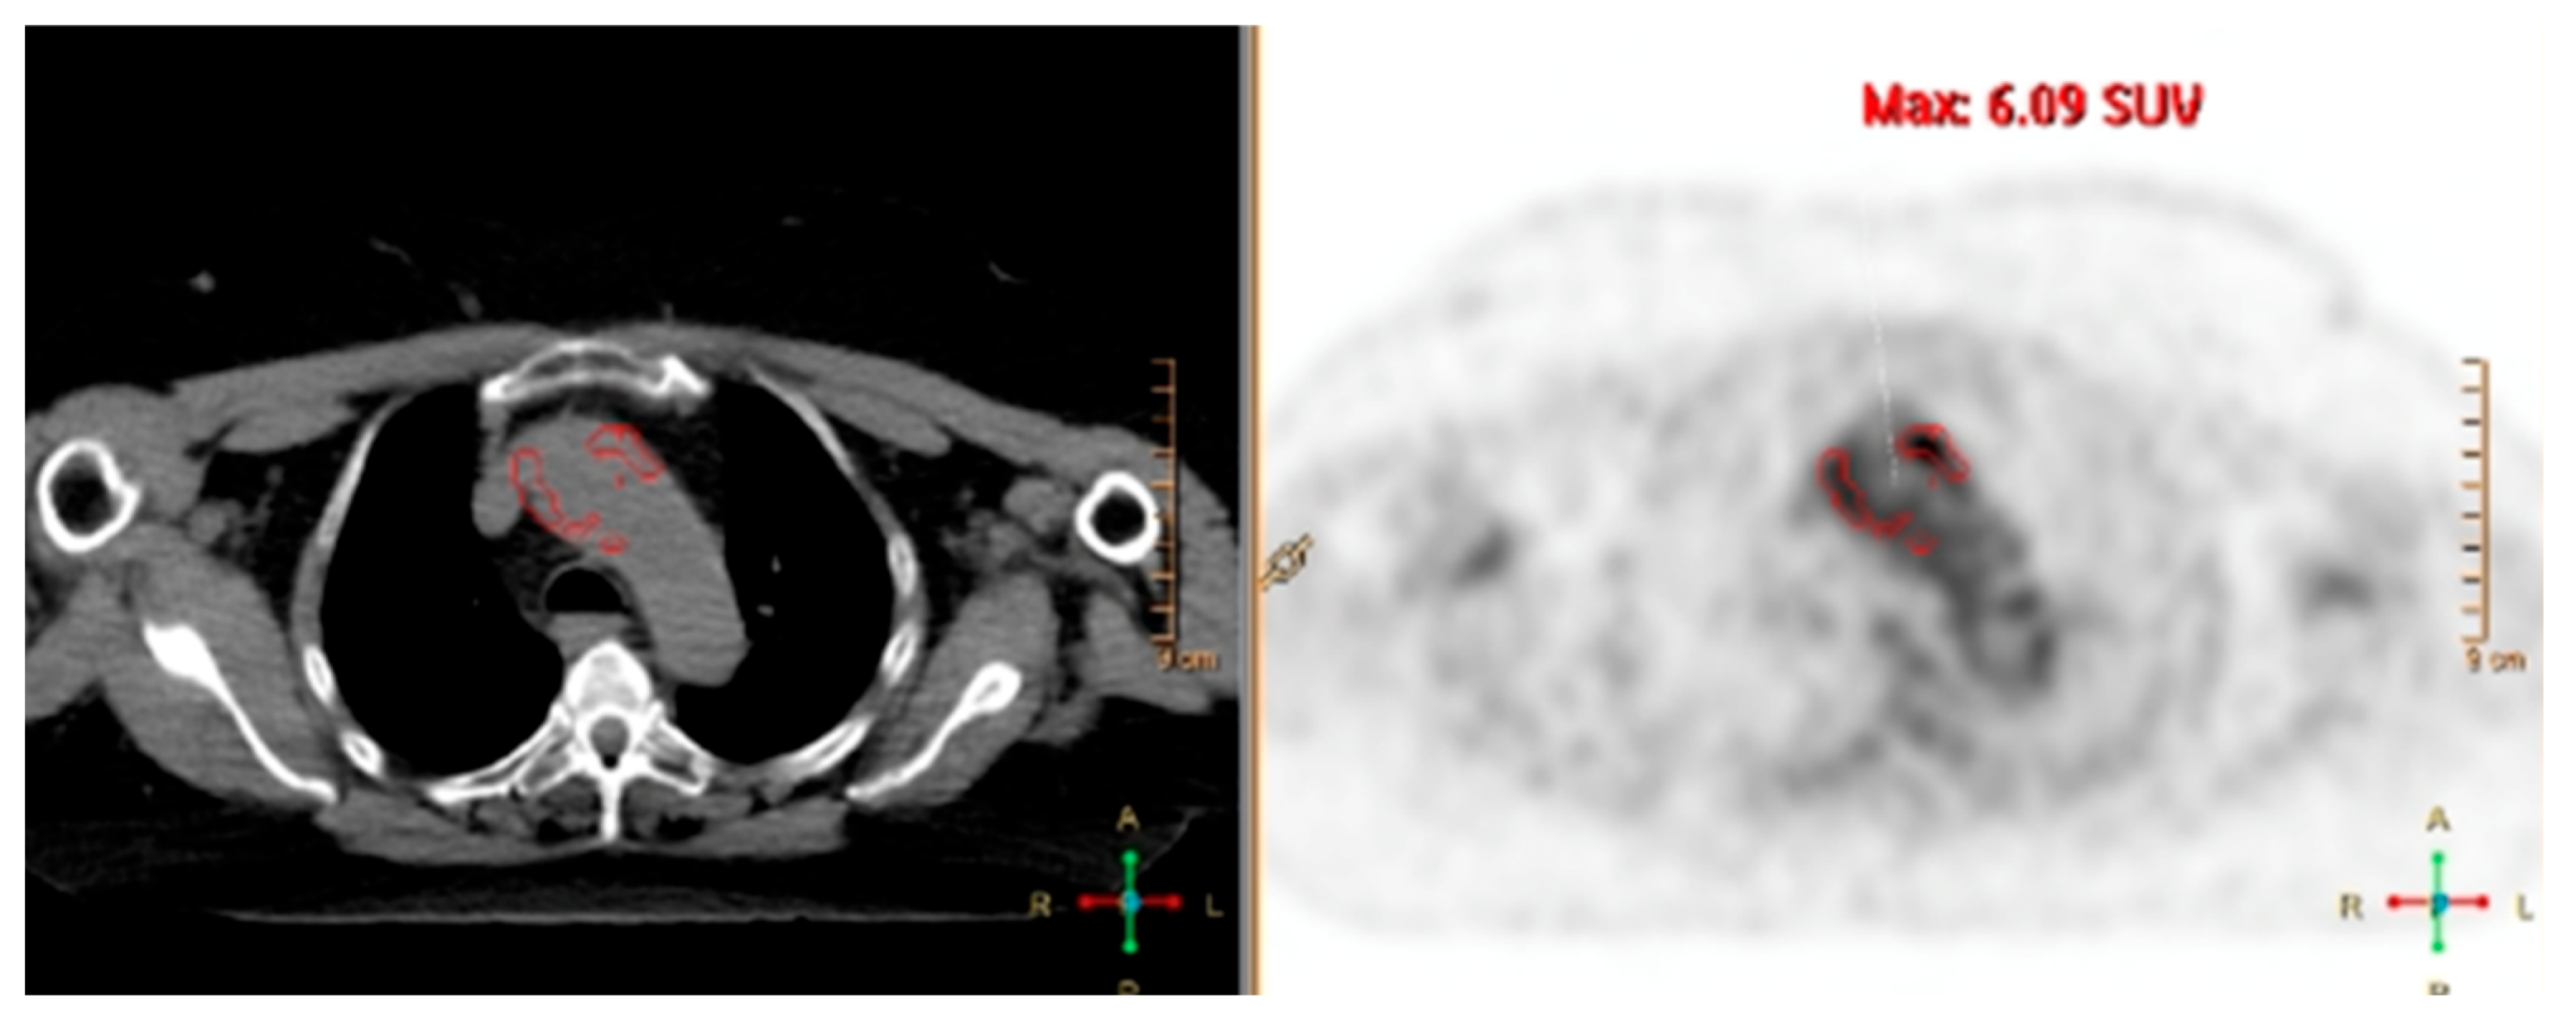

4. Fluorine-18-Fluorodeoxyglucose PET (FDG-PET)

4.1. Giant Cell Arteritis

4.2. Takayasu Arteritis